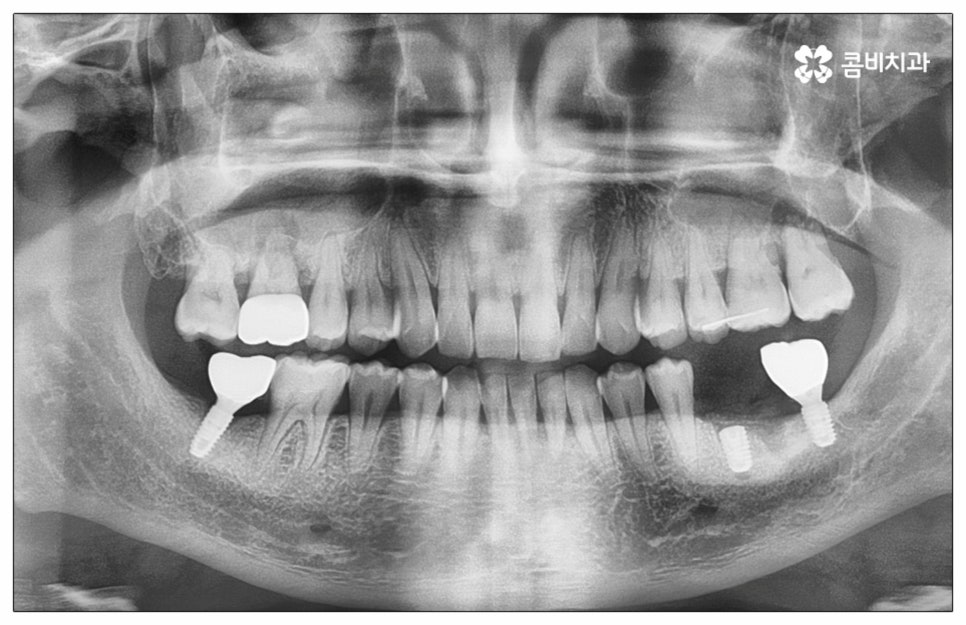

예전에는 이런 상황에서 틀니를 많이 이용하였으나 저작력 회복이 본래 자신의 치아 대비 20~30% 정도 밖에 되지 않고 잦은 탈락 위험 및 이물감, 잇몸을 눌러 장기적으로 잇몸뼈가 내려앉을 수 있다는 점 등 여러 가지 불편함이 있어 요즘은 임플란트 시술을 선호하시는 분들이 더 많아지고 있어요. 임플란트란 인체에 무해하며 잇몸뼈와 잘 결합하는 인공 치근을 잇몸뼈에 직접 식립하고 그 위로 기둥이 되는 중간 지대주와 치아 머리가 되는 크라운 보철물을 연결하여 인공 치아를 만들어 주는 시술을 말하는데, 자연 치아의 80% 정도 저작력 회복이 가능하기 때문에 식사를 할 때 음식을 크게 가리지 않아도 된다는 점 그리고 심미적으로 봤을 때 주변 치아와 자연스럽게 어우러진다는 점 때문에 각광을 받고 있습니다. 게다가 건강 보험 가입자이면서 만 65세 이상 부분 무치악 환자라면 평생 임플란트 2개까지 보험 적용을 받아 비용 부담을 줄일 수 있기 때문에 더욱 더 수요가 늘어나 이제는 치아 상실에 대체하는 대표적인 방법으로 임플란트 시술이 꼽히고 있는데요.

많이 대중화 되었다고 해도 임플란트 수술 자체가 술자의 숙련도에 크게 영향을 받는 복잡하고 고난도의 진료인 것은 틀림이 없기 때문에 담당 의료진이 해당 분야 임상 경험이 풍부한지, 뛰어난 기술력과 노하우를 가지고 있는지 꼼꼼하게 체크해 보실 필요가 있어요. 특히 노년층의 경우 당뇨, 고혈압 등 만성 질환을 앓고 있는 경우가 많아 혹시 상시 복용하고 있는 약이 있는지, 현재 환자 개개인의 상태는 어떤지, 사전 처치가 필요한 부분은 없는지 등등 수술 조건을 좀 더 까다롭게 평가한 후 환자분들과 이에 대해 충분히 상담하고 맞춤형 치료 계획을 세워 진행해야 하며 이를 위해 3D CT 와 같은 디지털 검진 장비를 통해 구강 내부 구조를 면밀하게 살피고 방대한 임상 데이터를 축적한 정품 임플란트 재료를 이용하여 연령이나 회복 정도를 살펴보면서 체력적 부담을 줄이는 방향으로 무리하지 않게 식립하는 것이 무엇보다 중요하다고 할 수 있습니다.

이때 추가 수술은 비급여 항목으로 건강보험임플란트 대상에서 제외되니 이에 대해서도 꼼꼼하게 살펴보시고 정밀 검진 후 담당 의료진과 자신의 상황에 대해서 충분하게 상담해 보시길 권유드리고 있습니다. 추가 수술의 대표적인 예로는 뼈이식 수술이 있는데요. 이것은 임플란트를 식립할 때 바탕이 되는 잇몸뼈의 높이나 폭, 밀도 등이 부족하다면 먼저 이를 보충해 주고 나서 임플란트를 심어주는 과정을 의미하며 같은 이유로 식립 성공률이나 장기적인 안정성을 높이기 위해 꼭 필요한 사전 처치, 즉 상악동 거상술 및 치주 질환 관련 수술 등을 먼저 해야 한다면 이 역시 추가 수술의 범주로 들어가니 자신의 상황에 대해서 상세하게 알아보실 필요가 있어요.